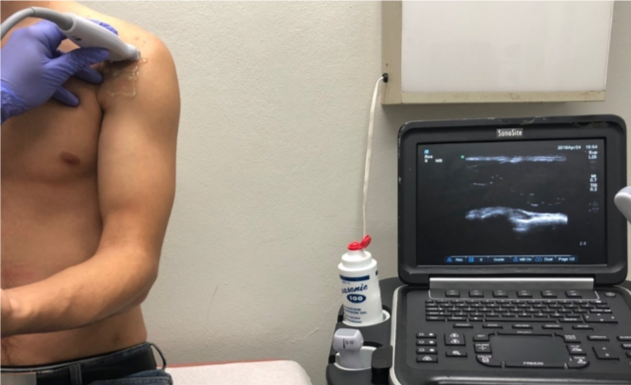

Bicipital tendinitis is a condition caused by inflammation of the long head of the biceps muscle’s tendon. It’s commonly caused by sudden overuse of the muscle and rotator cuff pathology such as muscle or tendon tears, chronic impingement, multidirectional shoulder instability, calcifications, and deconditioning. Signs in physical examination correlating with bicipital tendinitis are pain at the bicipital groove and a positive provocative test such as Speed’s test and Yergason’s test, although studies have shown that their sensitivity might be poor.1